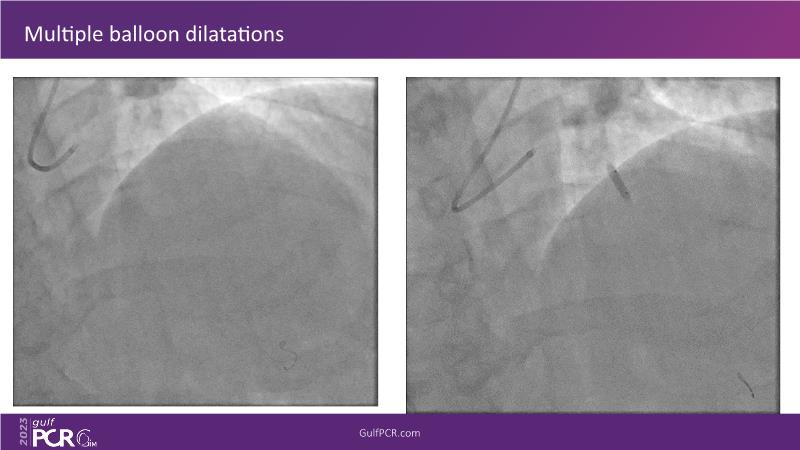

- To understand novel tools and techniques for effective management of bifurcation lesions and long diffused lesions using dedicated stenting solutions